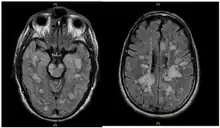

| Fulminating ADEM showing many lesions. The patient survived, but remained in a persistent vegetative state | |

ADEM produces multiple inflammatory lesions in the brain and spinal cord, particularly in the white matter. Usually these are found in the subcortical and central white matter and cortical gray-white junction of both cerebral hemispheres, cerebellum, brainstem, and spinal cord,[16] but periventricular white matter and gray matter of the cortex, thalami and basal ganglia may also be involved.